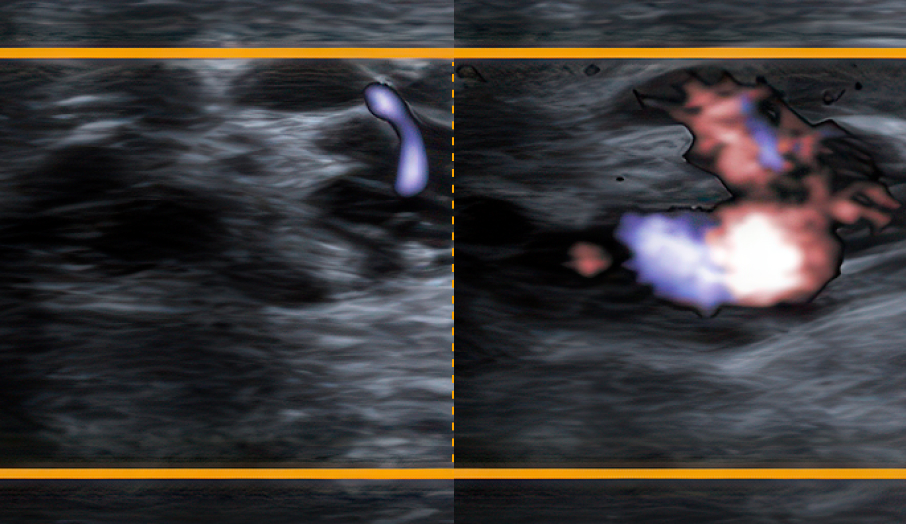

네. 정계정맥류는 건강보험 적용이 가능한 질환입니다. 다만 병원에서 시행하는 추가 검사나 일부 치료 방법에 따라 비급여 비용이 포함될 수 있습니다.

정계정맥류 수술은 보통 현미경 정계정맥류 수술 방식으로 진행되는 경우가 많습니다. 건강보험이 적용되는 질환이기 때문에 개인 부담 비용은 대략 수십만 원 정도 수준이며, 검사나 입원 여부에 따라 비용이 달라질 수 있습니다

정계정맥류 치료 비용은 수술 방법, 병변의 정도, 입원 여부 등에 따라 달라질 수 있습니다. 일반적으로 건강보험 적용 시 약 30만 원~70만 원 정도의 본인 부담 비용이 발생할 수 있으며, 검사 및 치료 방법에 따라 비용 차이가 있을 수 있습니다. 정확한 비용은 진료 후 안내드립니다.